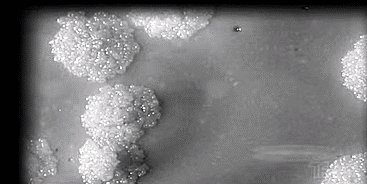

咳嗽、咳痰、乏力……先是爸爸得病 ,之后15岁的儿子确诊 ,妈妈、3个姐姐也宣布“中招” .....去年开始 , 正在上初三的小王就咳嗽不停 , 能咳出痰液 , 一天即使啥都没做 , 也会很疲乏 。小王很紧张 , 赶紧到广东省深圳一家定点医院就诊 , 医生一查 ,肺部有感染。而且小王说 , 他的爸爸也有类似的病征 。医生觉得不妙 , 随即通知小王的家人也尽快到医院检查 。果然 , 小王的妈妈、3个姐姐都得了同样的病 。而且这病也是一种呼吸道传染病 , 病原体主要通过 飞沫传播 !这到底是啥病?结核病!(最常见的是肺结核) 它的病原体叫结核菌 。肺结核与新冠肺炎同样属于呼吸道传染病 , 存在着很多共同之处 , 比如都有咳嗽、发热、肺部感染症状 , 传播方式以呼吸道飞沫传播为主 , 病人都需要戴上口罩 。——深圳市第三人民医院肺科门诊主任邓永聪世卫组织的2019年全球结核病报告显示 ,结核菌的潜伏感染人群 ,在全球约有17亿 ,相当于每4个人就有1个感染 (带菌但没发病) 。在我国法定的甲、乙类传染病中 ,肺结核在发病数和死亡数上 , 均位列第2 。目前全球的结核病防治工作任重道远 ,中国每年发病数为86万人左右 , 是当下新冠肺炎患者的十倍, 希望大家慎重对待 。▽